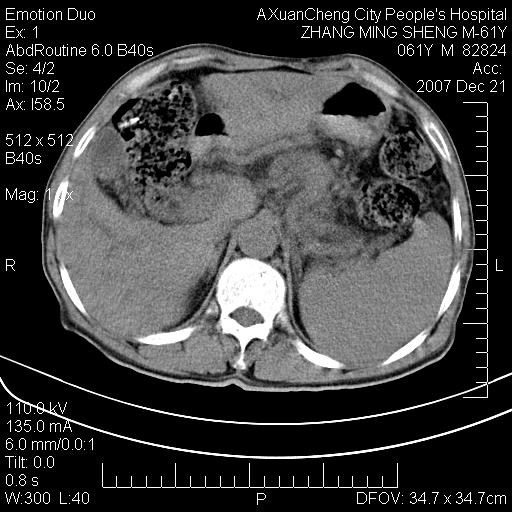

标题: CT11031:M61Y,胰腺占位 [打印本页]

标题: CT11031:M61Y,胰腺占位

大家侃侃门静脉和胆管系统怎么回事,肝内转移?

胰腺癌肝转移

肝硬化,门脉高压,脾肿大;弥漫性肝癌,肝内、门脉、腹膜后淋巴结转移,肝内外胆管扩张,胰头区占位,建议mr检查

胰腺癌伴肝内转移;门脉、肠系膜上v癌栓形成。

考虑为:胰腺癌伴肝脏转移、腹膜后淋巴结转移,门静脉及肠系膜上静脉瘤栓形成。

胰体尾癌伴肝内转移,门静脉及肠系膜上静脉瘤栓形成.

肝硬化,脾大. 胰腺癌伴肝内转移;门脉、肠系膜上v癌栓形成。